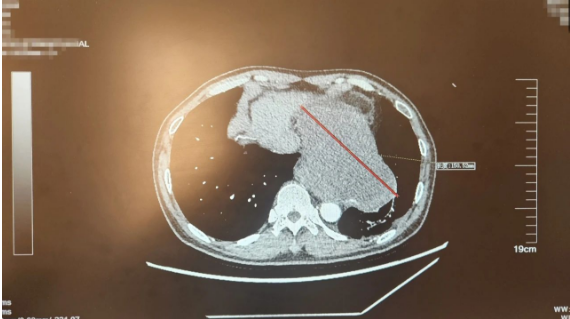

11月14日,一台“步步惊‘心’”的手术正在北京天坛医院手术室进行。手术台上躺着的是61岁的老康,他左侧胸腔内的肿瘤最大直径15厘米,几乎有成人两个拳头大小,与老康的心脏、胸主动脉、左下肺静脉、食管纠缠在一起,稍有不慎就可能引起大出血、心律失常甚至心跳骤停。